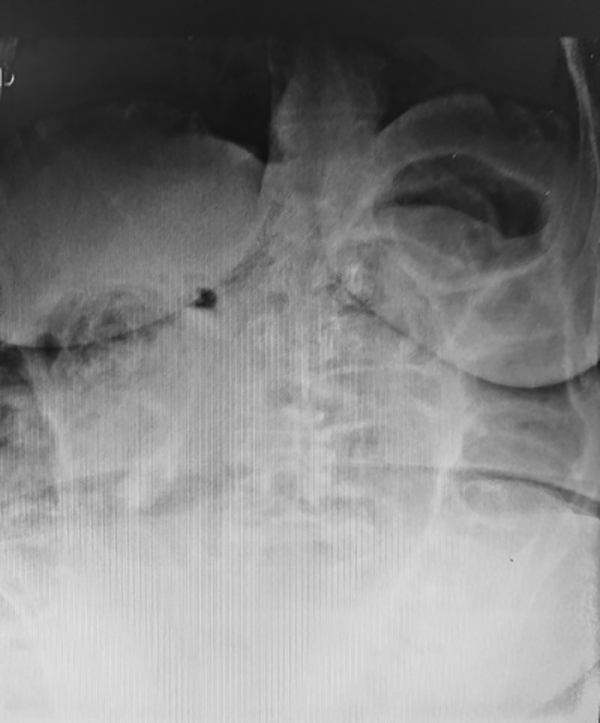

Ingresa por guardia una paciente femenina 71 años de edad, con antecedentes de dolor abdominal y cambios en el ritmo evacuatorio, con heces acintadas, de tres meses de evolución, anexohisterectomía (no recuerda la causa), cirugía bariátrica y colecistectomía. Presenta dolor abdominal de tipo cólico difuso de cinco días de evolución asociado a distensión abdominal, náuseas y falta de eliminación de gases. Nunca se había realizado una videocolonoscopía. Ingresa con signos vitales normales. Presenta el abdomen distendido, globoso, con dolor difuso a predominio fosa iliaca izquierda con defensa parietal, timpánico generalizado y ruidos hidroaéreos disminuidos en intensidad. En el tacto rectal no se hallan lesiones ni evidencia de sangrado. Los estudios complementarios revelan niveles hidroaéreos colónicos sin aire hacia distal (Figura 1). Se colocan una vía periférica, una sonda nasogástrica y una vesical. Dada la evolución clínica y la no respuesta al tratamiento médico junto con los hallazgos imagenológicos se decide realizar una laparotomía de urgencia. Durante el procedimiento quirúrgico se evidencia una lesión de aspecto inflamatorio en rectosigma que involucra al intestino delgado (Figura 2). Se realiza una cirugía de Hartmann. La paciente presenta hundimiento de colostomía y se realiza reconfección de la misma a las 48 horas. El estudio anatomopatológico informa que la pared colónica presenta focos de endometriosis y adherencia a parénquima ovárico y tubárico; diverticulosis; y parénquima ovárico con cuerpo albicans, sin evidencia de lesión neoplásica colónica. Durante su internación intercurre con neumonía intrahospitalaria y fallece durante la internación.

Figura 1: Niveles hidroaéreos colónicos sin aire distal, compatibles con suboclusión intestinal.